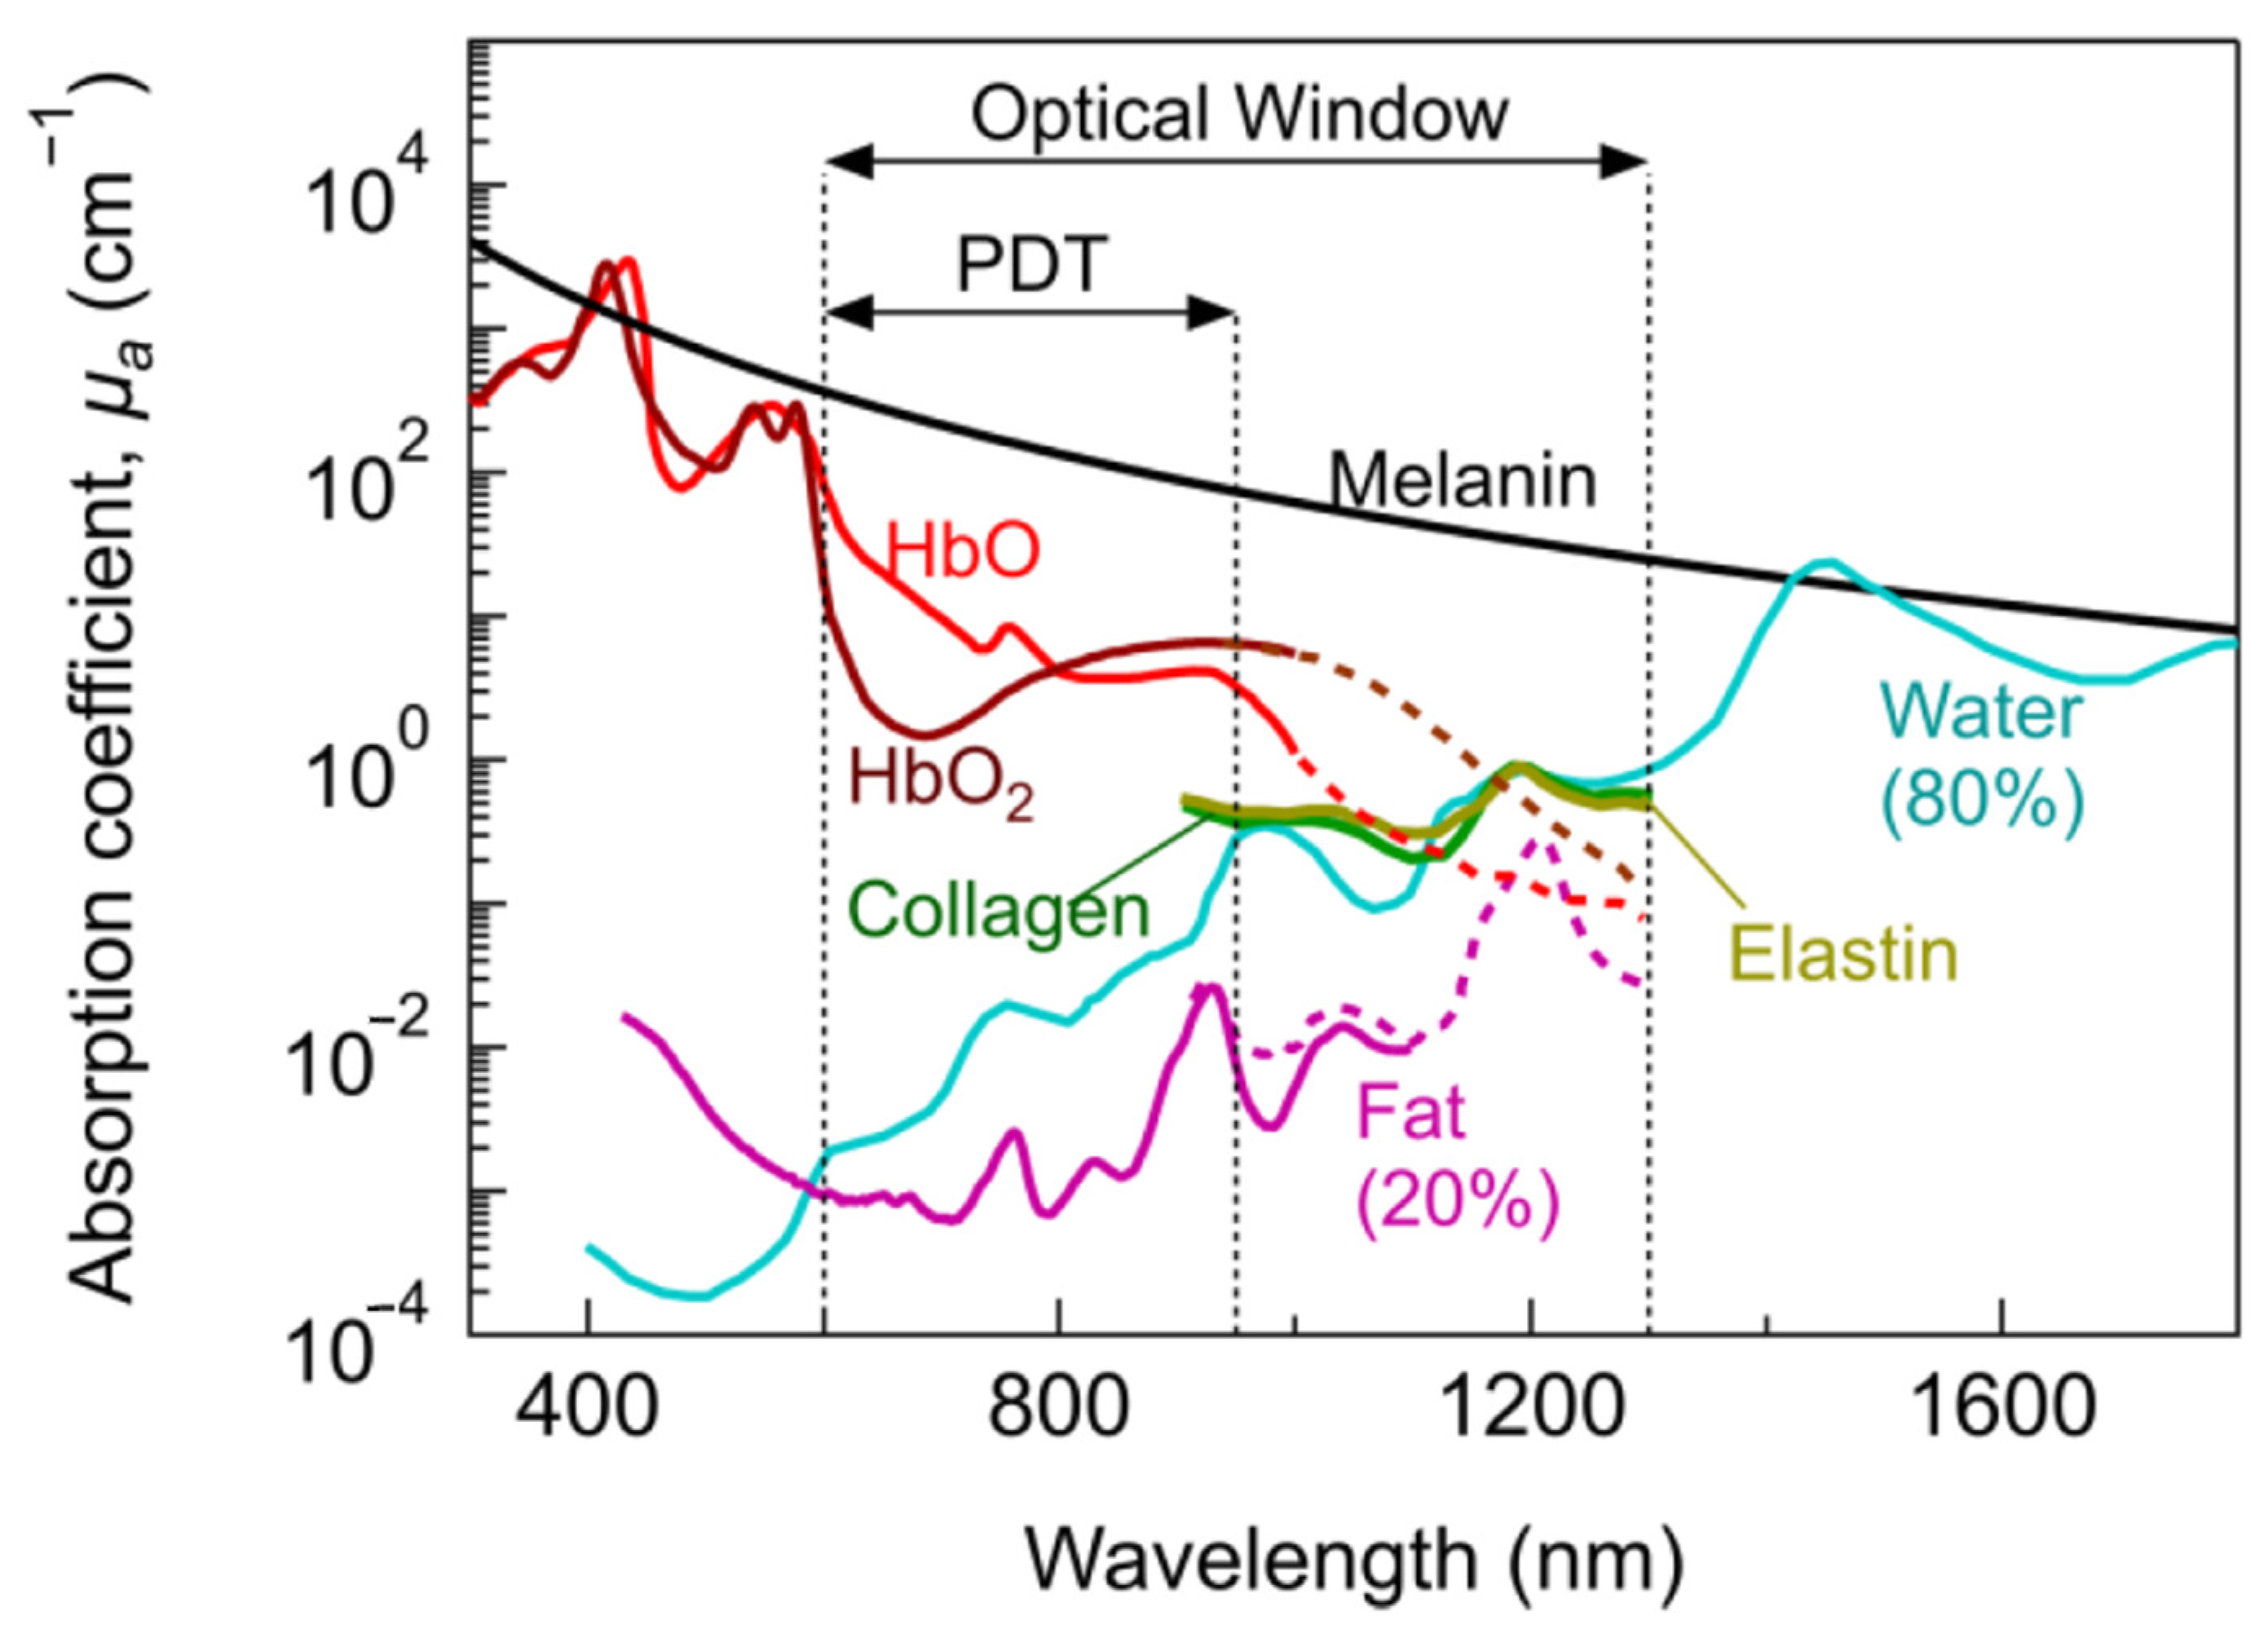

- Bashkatov, A.N.; Genina, E.A.; Kochubey, V.I.; Tuchin, V.V. Optical Properties of Human Skin, Subcutaneous and Mucous Tissues in the Wavelength Range from 400 to 2000 nm. J. Phys. Appl. Phys. 2005, 38, 2543–2555. [Google Scholar] [CrossRef]

- Smith, A.M.; Mancini, M.C.; Nie, S. Second Window for in vivo Imaging. Nat. Nanotechnol. 2009, 4, 710–711. [Google Scholar] [CrossRef] [PubMed] [Green Version]

- Welsher, K.; Sherlock, S.P.; Dai, H. Deep-Tissue Anatomical Imaging of Mice Using Carbon Nanotube Fluorophores in the Second near-Infrared Window. Proc. Natl. Acad. Sci. USA 2011, 108, 8943–8948. [Google Scholar] [CrossRef] [PubMed] [Green Version]